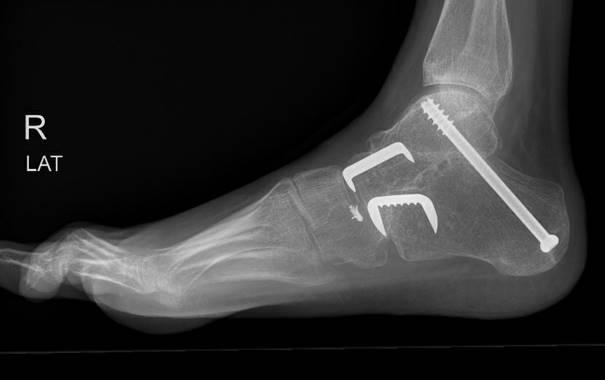

Voorbeeld van een röntgenfoto na de operatie

Er worden meestal drie incisies gemaakt: één aan de buitenkant, één aan de binnenkant van de voet en één onder de hiel. Hierna wordt het kraakbeen van het onderste sprong- en middenvoetsgewricht geheel verwijderd. De botten worden met meerdere schroeven en eventueel één of meerdere krammen in de juiste positie vastgezet. De huid wordt meestal gesloten met hechtingen die vanzelf oplossen.